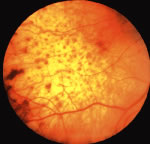

Metastatic cancer to the retina, which has rarely been reported,8,13 reaches the retina by either direct invasion from the adjacent choroid or by tumor emboli through the central retinal artery. The retinal tumors may appear as patchy yellow lesions associated with hemorrhage or exudate.

Sometimes there are overlying clumps of tumor cells in the vitreous such as in cases of cutaneous melanoma metastatic to the retina. The differential diagnosis includes cotton-wool spots, vascular obstructions, and retinitis.